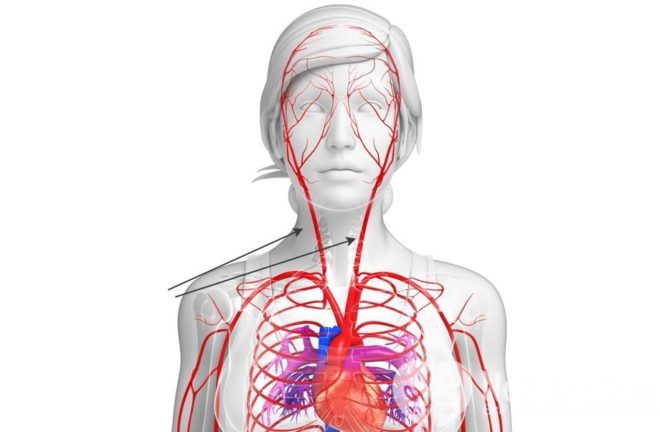

Сонная аорта является крупным сосудом, который имеет мышечно-эластический тип. С ее помощью обеспечивается питание таких важных частей тела, как голова и шея. От кровотока сонной артерии зависит работоспособность головного мозга, а также таких органов, как глаза, щитовидная железа, язык, паращитовидная железа.

О том, где находится сонная артерия должен знать каждый человек. В данном случае необходимо помнить, что вены и артерия – это абсолютно разные вещи. Местом расположения общей аорты является шея. Она характеризуется наличием двух одинаковых сосудов. С правой стороны начинается вена с брахиоцефального ствола, а с левой – от аорты.

Обе артериальные вены характеризуются идентичным анатомическим строением. Они характеризуются вертикальным направлением вверх через грудную клетку. Над грудинно-ключично-сосцевидной мышцей находятся внутренняя и наружная сонная аорты.

Расположение сонных артерий на шее осуществляется с левой и правой сторон. Для того чтобы знать, как найти сонную артерию, необходимо знать ее расположение. Под грудинно-ключично-сосцевидной мышцей проходит основная аорта. Над щитовидным хрящом она разделяется на две ветви. Данное место имеет название бифуркация. В этом месте наблюдается нахождение рецепторов-анализаторов, которые сигнализируют об уровне давления внутри сосуда.